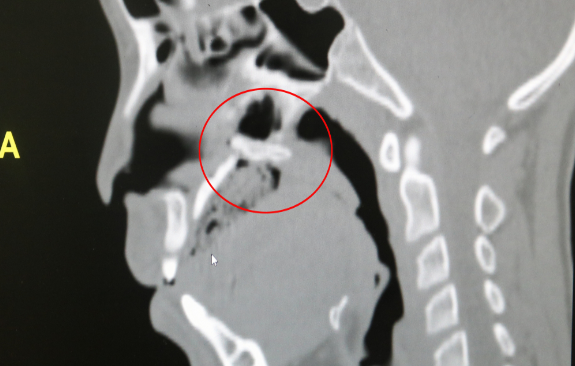

Bé trai 10 tuổi thủng vòm họng do ngã xe đạp

Bé trai ở Quảng Ninh bị thủng vòm họng, chấn thương nặng, chảy máu nhiều do ngã xe đạp khiến tay lái đâm vào miệng.